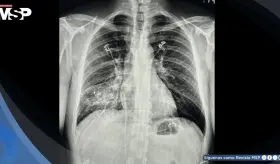

Los médicos encontraron casi un litro de pus alrededor del corazón, confirmando una pericarditis purulenta que evolucionó a una forma constrictiva, impidiendo al corazón latir con normalidad.